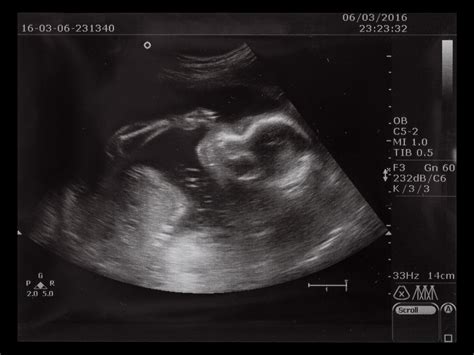

Approfondendo una delle prestazioni diagnostiche prenatali più rilevanti, l'amniocentesi, è cruciale comprendere i criteri che ne definiscono la gratuità all'interno del Servizio Sanitario Nazionale, in linea con gli aggiornamenti del 2017 del Ministero della Salute e le modalità operative della Regione Campania. Questa procedura, che comporta il prelievo di una piccola quantità di liquido amniotico per l'analisi cromosomica e genetica del feto, è oggetto di specifiche regolamentazioni volte a garantire un uso appropriato e mirato delle risorse.

Il test combinato, introdotto come prestazione universale nel 1° trimestre per la diagnosi prenatale, offre a tutte le donne un primo screening essenziale. Esso combina i risultati di un prelievo di sangue materno, che analizza specifici marcatori biochimici, con un'ecografia dettagliata per valutare la translucenza nucale del feto. Questo approccio integrato fornisce una stima personalizzata del rischio, orientando le decisioni successive e identificando le donne che potrebbero beneficiare di ulteriori indagini invasive come l'amniocentesi, garantendone la gratuità solo quando clinicamente giustificata.